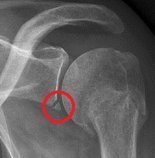

What is a Bankart Lesion and what kind of injury is it associated with?

fracture of the anterior inferior glenoid following impaction of the humeral head against the glenoid (anterior shoulder dislocation)

What is a Hill-Sachs lesion?

dent in the humeral head

compression chondral injury of the posterior superior humeral head following impaction against the glenoid